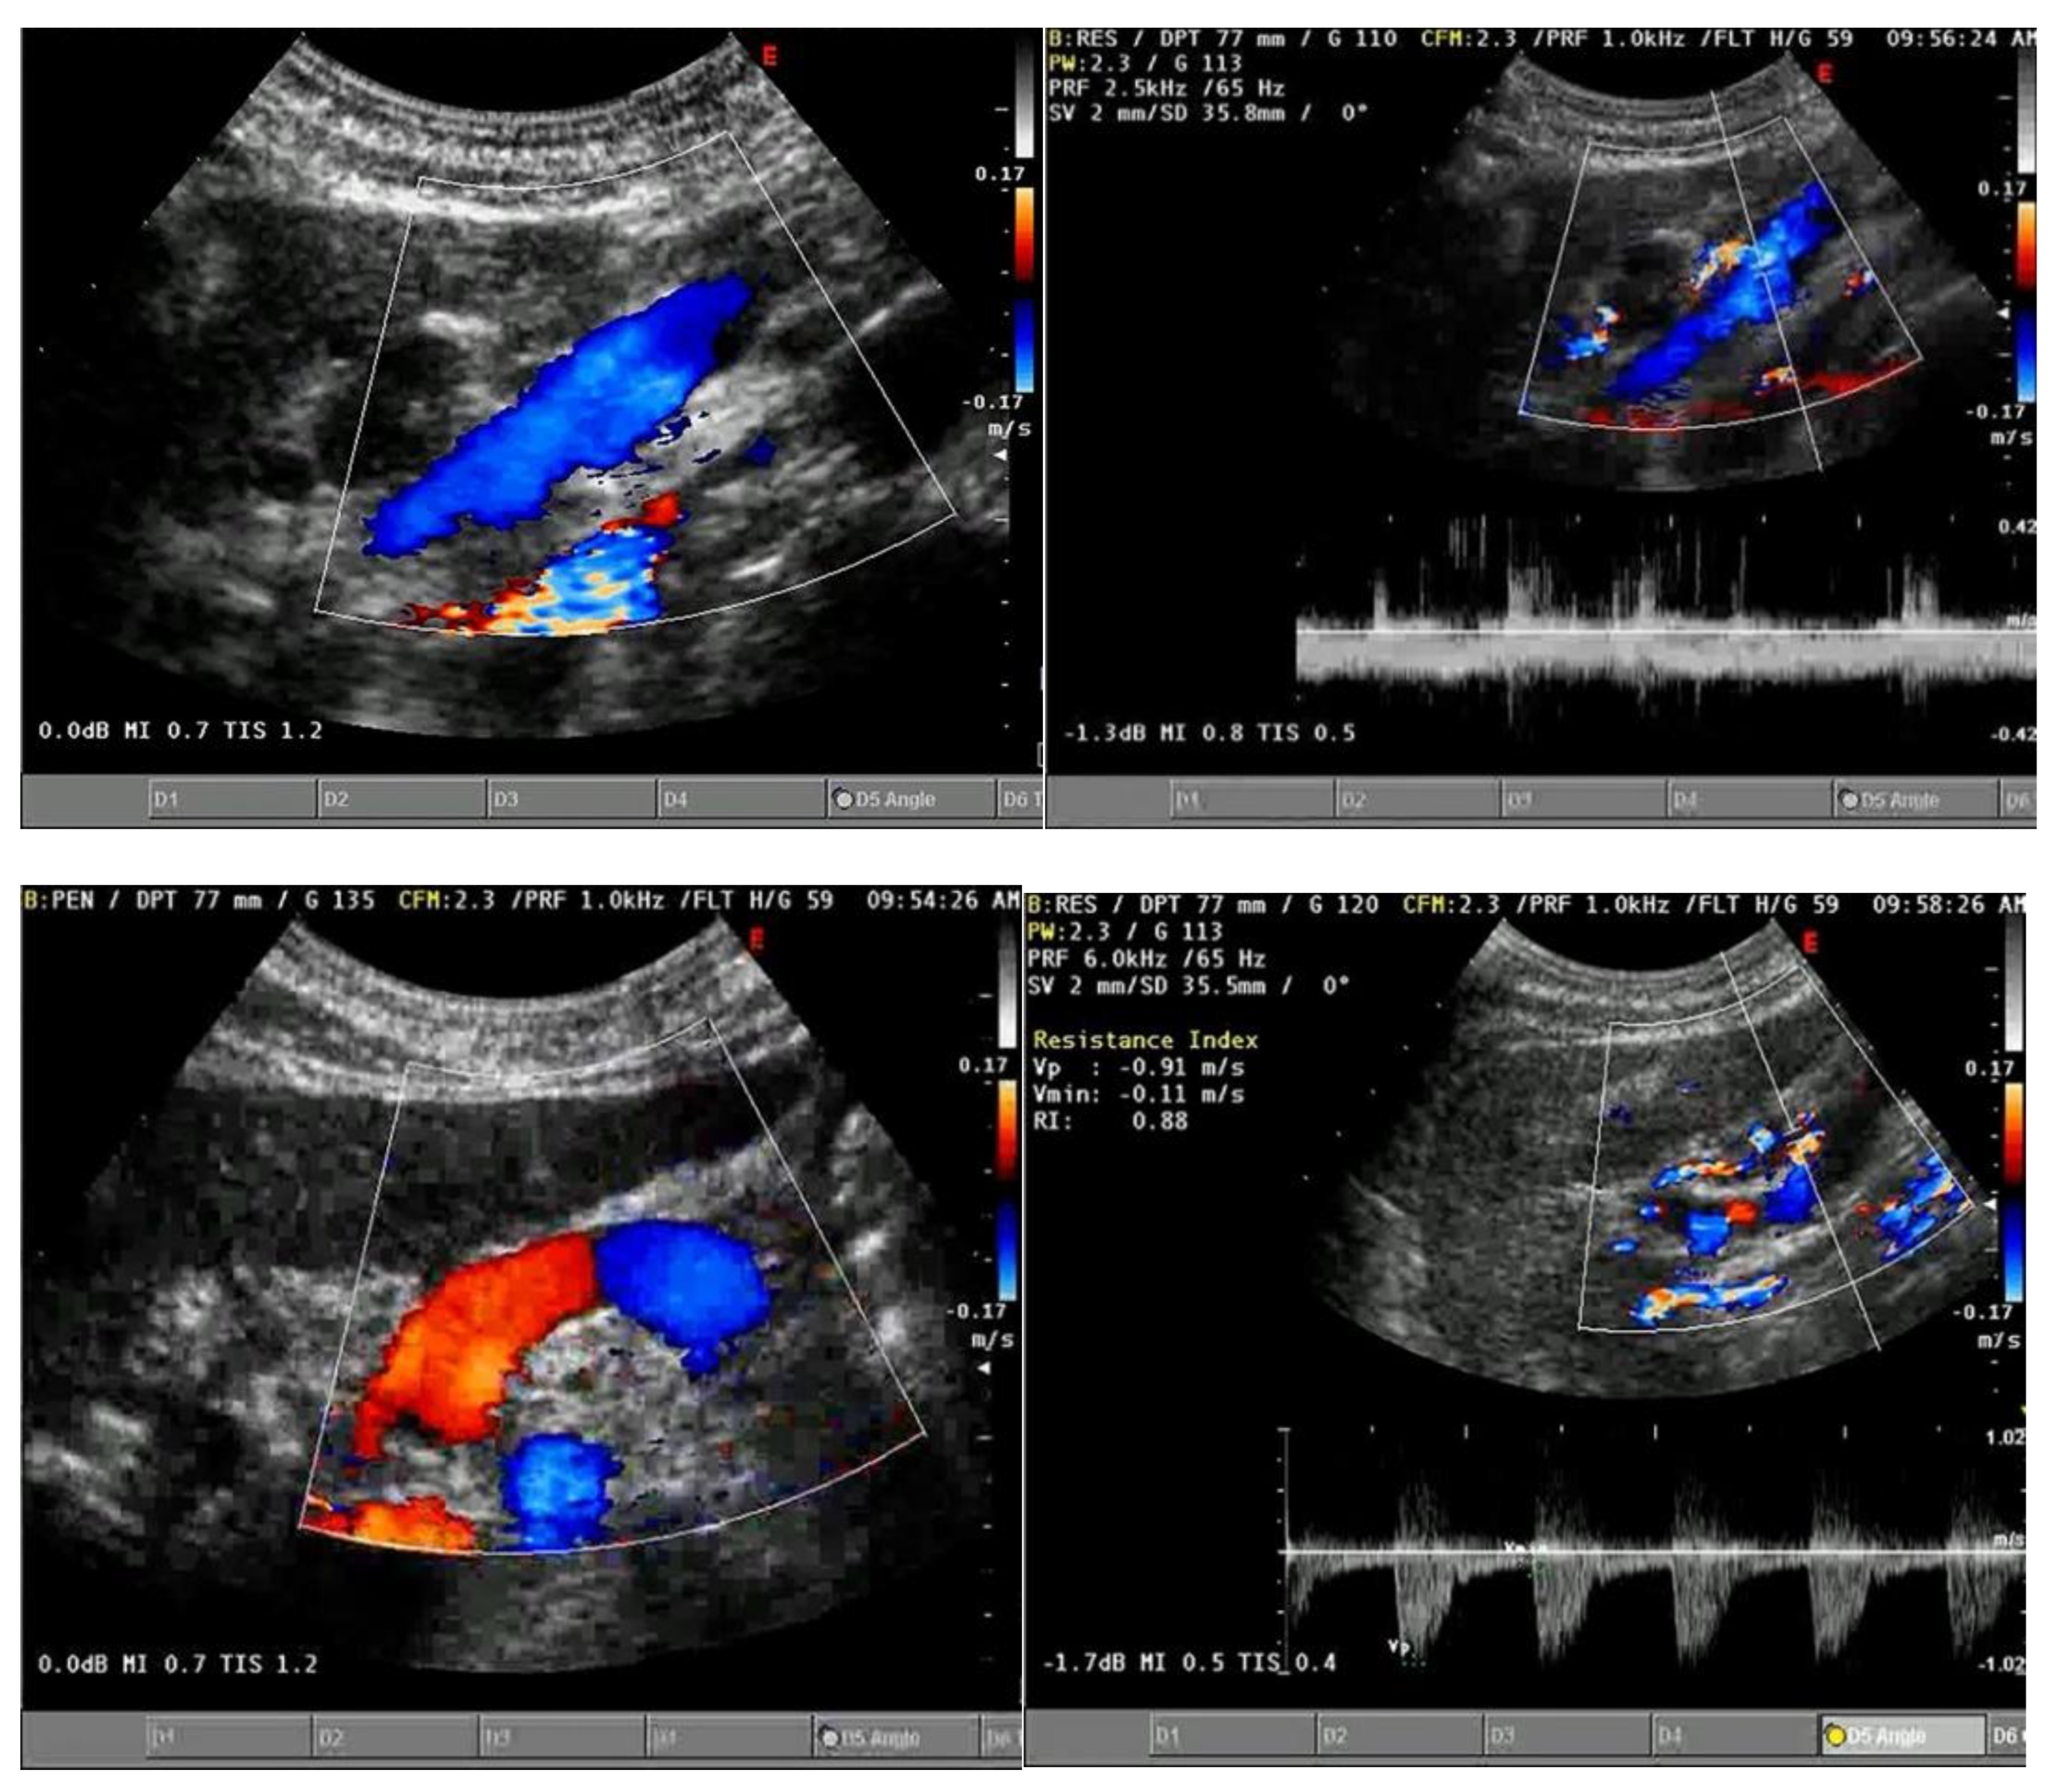

3.1.2. Ecocolordoppler and Spectral Velocity Variations:

PORTAL VEIN:

4. Absent (Aphasic) Portal Venous Flow:

- Hosoki, T.; Arisawa, J.; Marukawa, T.; Tokunaga, K.; Kuroda, C.; Kozuka, T.; Nakano, S. Portal blood flow in congestive heart failure: pulsed duplex sonographic findings. Radiology 1990, 174, 733-736. [CrossRef]

- Abu-Yousef, M.M.; Milam, S.G.; Farner, R.M. Pulsatile portal vein flow: a sign of tricuspid regurgitation on duplex Doppler sonography. AJR Am J Roentgenol 1990, 155, 785-788. [CrossRef]

- Gallix, B.P.; Taourel, P.; Dauzat, M.; Bruel, J.M.; Lafortune, M. Flow pulsatility in the portal venous system: a study of Doppler sonography in healthy adults. AJR Am J Roentgenol 1997, 169, 141-144. [CrossRef]

- Rengo, C.; Brevetti, G.; Sorrentino, G.; D'Amato, T.; Imparato, M.; Vitale, D.F.; Acanfora, D.; Rengo, F. Portal vein pulsatility ratio provides a measure of right heart function in chronic heart failure. Ultrasound Med Biol 1998, 24, 327-332. [CrossRef]

- Goncalvesova, E.; Lesny, P.; Luknar, M.; Solik, P.; Varga, I. Changes of portal flow in heart failure patients with liver congestion. Bratislavske lekarske listy 2010, 111, 635-639.

- Catalano, D.; Caruso, G.; DiFazzio, S.; Carpinteri, G.; Scalisi, N.; Trovato, G.M. Portal vein pulsatility ratio and heart failure. J Clin Ultrasound 1998, 26, 27-31. [CrossRef]

- Deschamps, J.; Denault, A.; Galarza, L.; Rola, P.; Ledoux-Hutchinson, L.; Huard, K.; Gebhard, C.E.; Calderone, A.; Canty, D.; Beaubien-Souligny, W. Venous Doppler to Assess Congestion: A Comprehensive Review of Current Evidence and Nomenclature. Ultrasound Med Biol 2023, 49, 3-17. [CrossRef]